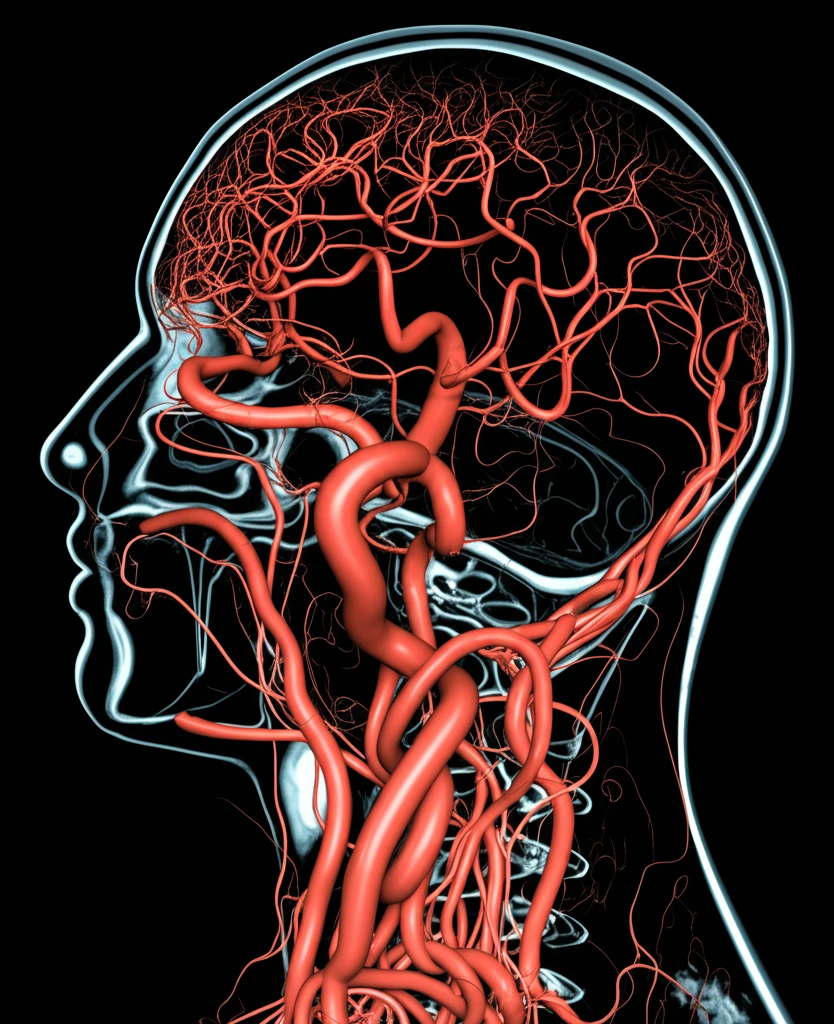

- 혈관 이상: 동맥류, 혈관 기형 등 혈관의 이상을 정확하게 진단하여, 추가적인 합병증을 예방하고 적절한 치료 계획을 수립하는 데 도움을 줍니다.